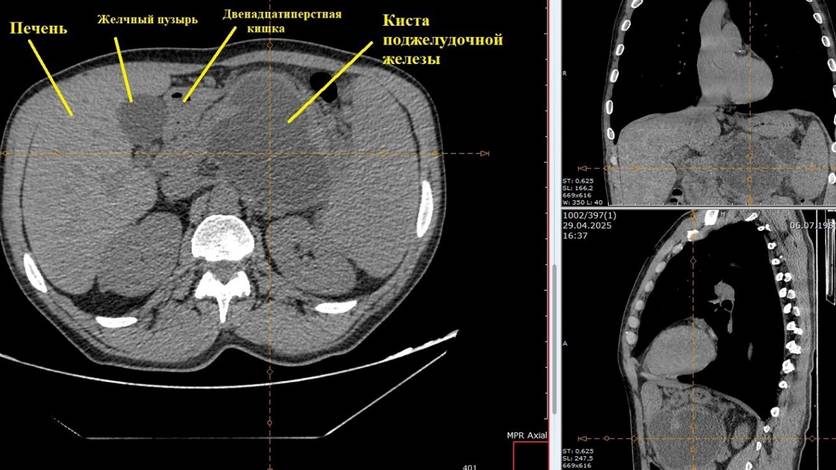

В Орле прооперировали пациента с огромной кистой на поджелудочной железе

43-летний мужчина поступил в больницу с острой болью в верхней части живота и левом подреберье.

В Орле успешно прооперировали пациента с крупной псевдокистой поджелудочной железы. Об этом сообщили в группе "Орловская областная клиническая больница".

43-летний мужчина поступил в хирургическое отделение с сильными болями в животе. У него уже были проблемы с поджелудочной железой. Обследование выявило большую кисту.

Хирурги провели операцию, используя видеолапароскопические технологии. Через небольшие разрезы им удалось восстановить нормальное пищеварение. Операция прошла успешно: боли прекратились, и пациент смог вернуться к привычному питанию. Сейчас его уже выписали из больницы.